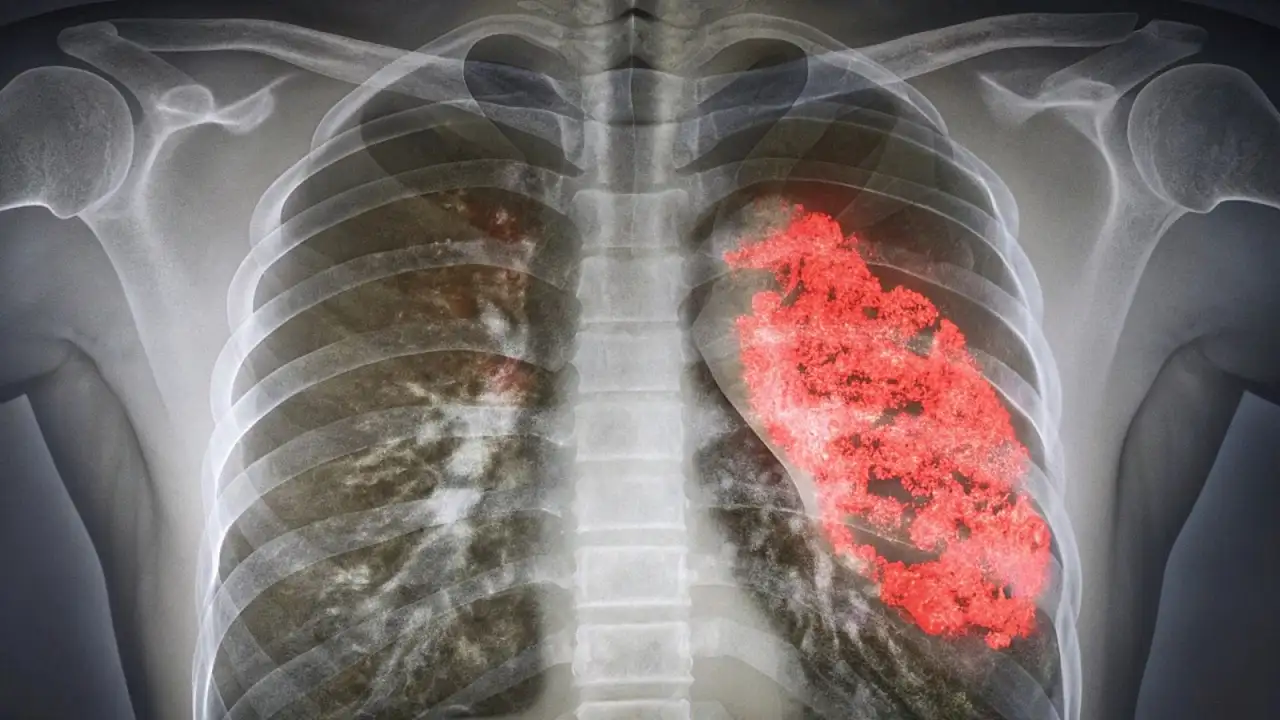

Bakanlık açıklamasında, pnömoninin akciğerlerdeki hava keseciklerinin iltihaplanması sonucu ortaya çıktığı ve özellikle risk grubundaki vatandaşlar için ciddi sonuçlara yol açabileceği vurgulandı.

Bakanlık ayrıca pnömoninin yalnızca yaşlılarda değil, bağışıklık sistemi zayıf olanlarda, KOAH ve astım gibi solunum rahatsızlığı bulunanlarda, sigara kullananlarda daha ağır seyredebildiğine dikkat çekti.